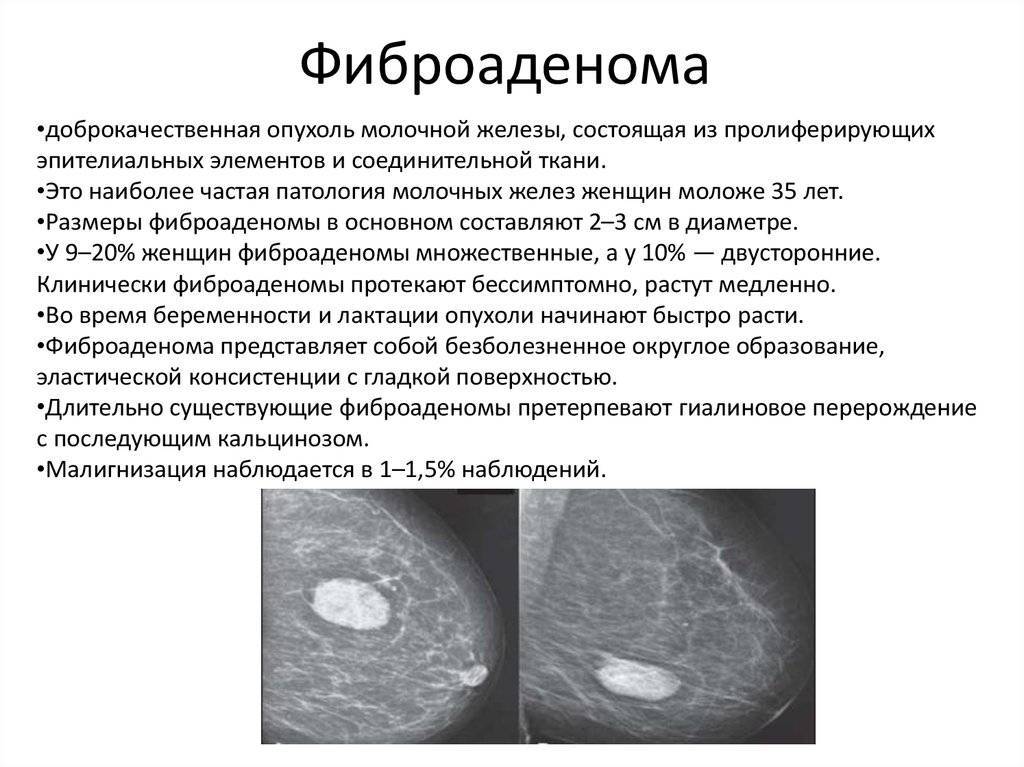

Новообразование в головном мозге. Презентация опухоль мозга. Опухоли головного мозга презентация. Злокачественная фиброаденома молочной железы. Фиброаденома молочной железы Размеры для операции. Фиброаденома молочной железы маммография. Листовидная опухоль гистология.

Злокачественная фиброаденома молочной железы. Фиброаденома молочной железы Размеры для операции. Фиброаденома молочной железы маммография. Листовидная опухоль гистология. Доброкачественная опухоль. Доброкачественныеопкхоли. Клетки, образующие доброкачественную опухоль:. Строение доброкачественной опухоли.